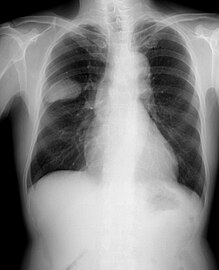

Small-cell carcinoma of the lung usually presents in the central airways and infiltrates the submucosa leading to narrowing of bronchial airways. Common symptoms include cough, dyspnea, weight loss, and debility. Over 70% of patients with small-cell carcinoma present with metastatic disease; common sites include liver, adrenals, bone, and brain.[20][21]

Small-cell carcinoma is most often more rapidly and widely metastatic than non-small-cell lung carcinoma[27] (and hence staged differently). There is usually early involvement of the hilar and mediastinal lymph nodes. [26] The mechanisms of its metastatic progression are not well-understood.[28]